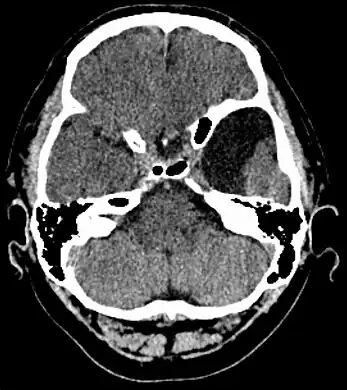

-

Male with complicated arachnoid cyst -

Arachnoid cyst as seen on a CT image of the brain -

Axial CT showing a typical arachnoid cyst left temporal